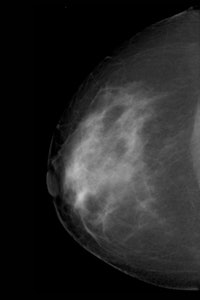

The other challenge is the value of mammography is limited, as these women have morphological features that differ from "normal" breast cancer and have dense breasts, thus making it more difficult to image on mammography. The researchers investigated whether adding ABUS twice yearly to the screening regimen would help these women in particular. ABUS was chosen over handheld ultrasound, because it's fast, standardized, and may be performed by nonradiologists with minimal training.